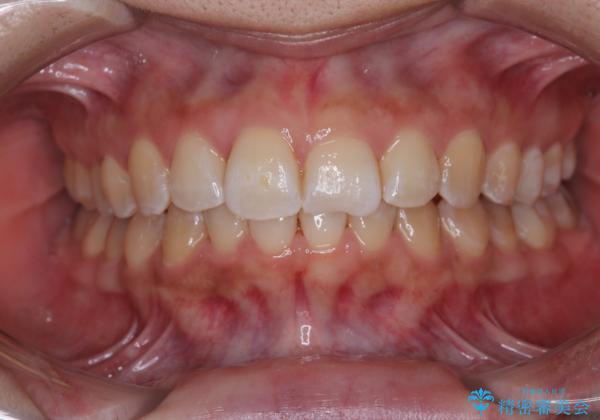

前歯のデコボコをインビザライン矯正で綺麗に改善

舌の突出癖改善がうまくいかず、途中で舌小帯の切除を行いました。

気になる段差を納得いくまで改善させたため、治療期間は長くなりましたが、綺麗な仕上がりとなりました。